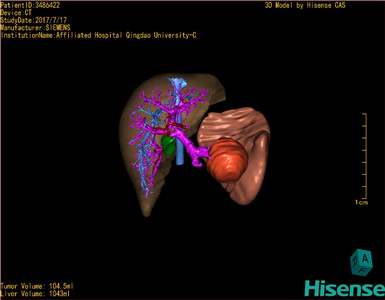

将0.625mm双源薄层CT资料的静脉期和动脉期Dicom格式文件导入海信CAS系统。

通过调节窗宽窗位调整CT序号,对肿瘤,肝实质,胆囊,下腔静脉,肿瘤,肝动脉、门静脉及肝静脉等进行三维重建;系统自动计算肿瘤体积和肝脏体积。

模拟手术操作,自动计算切除肿瘤体积。肝脏体积为1096ml,胰腺肿瘤体积为115.5ml,通过比对12-13岁正常肝脏体积为1116.86±158.78 ml,通过术前模拟手术,精准判断切除后肝脏体积无明显变化,避免肝衰竭发生。

术前三维重建:

重建图片